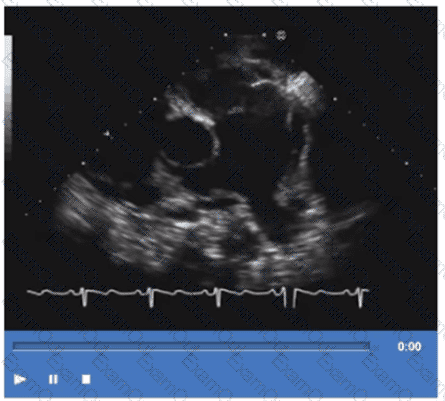

In which view is the superior vena cava visualized in its long axis?